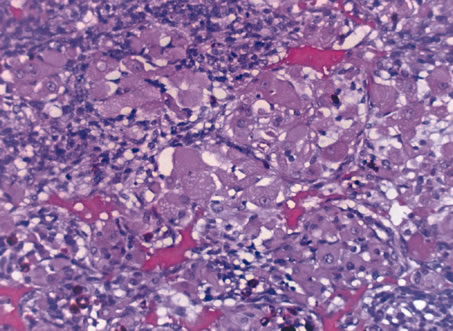

Inflammatory conditions may also lead to iris nodules. Patients suffering from fungal endophthalmitis may demonstrate an irregular yellow-white mass on the iris. Histologically, these appear as necrotizing granulomas containing mycotic agents (Fig. 2). In juvenile xanthogranuloma, a yellowish-gray iris lesion may be associated with spontaneous hyphema, and histopathologically the nodules demonstrate diffuse histiocytic infiltrate (Fig. 3). Multinucleated giant cells displaying peripheral foamy cytoplasm are also noted; these cells are known as Touton giant cells.29 The giant cells and the histiocytes contain lipid that can be demonstrated by oil red O stain.

Fig. 3. Juvenile xanthogranuloma. The iris is infiltrated by histiocytes, which form nodular aggregates on the anterior surface of the iris. (Hemotoxylin-eosin ×25.) Inset (×200) shows oil red O-positive histiocytes.